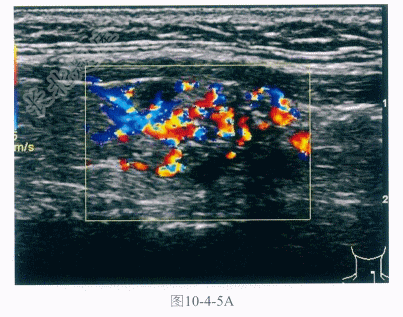

- 多项选择题2.该患者进行了超声及CT检查(图10-4-5,彩图10-4-5A),超声提示甲状腺左叶低回声为主肿物,形态不规则,回声不均匀,内可探及多个微小强回声光点及丰富血流信号,颈部可见低回声结节,内可见无回声区,CT可见甲状腺左叶边缘模糊结节,密度不均匀,颈部可见多发肿大淋巴结,明显强化,该病可能的诊断为: